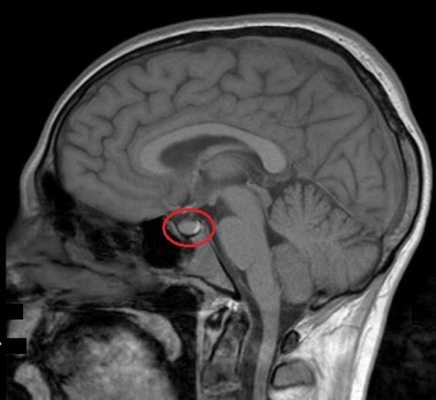

МРТ гипофиза при краниофарингиоме: сканы в разных проекциях

Магнитно-резонансная томография - один из высокоинформативных способов инструментальной диагностики. Исследование показывает мельчайшие изменения в структуре органов, предположительный характер патологии, взаимоотношение с близлежащими структурами. Скульптурирование многоплоскостных изображений во время МР-сканирования подразумевает использование принципа ядерно-магнитного резонанса, но не рентгеновских лучей. Атомы водорода в клетках воды, попав в поле, генерируемое аппаратом, начинают перестраиваться, при обретении привычного положения выделяется определенное количество энергии, которое фиксируют датчики, а обрабатывает компьютерная программа. Какого-либо вредоносного воздействия на организм во время диагностической процедуры нет, при условии отсутствия в теле металлических составляющих. Врач получает возможность рассматривать патологический очаг в любой плоскости, что невозможно при обычной рентгенографии или КТ.